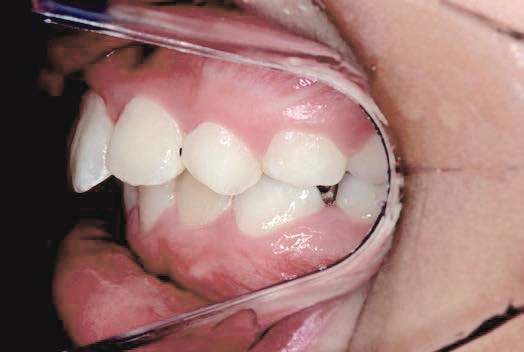

現役歯科医師の愛娘さんの治療

Nさん (矯正開始時:8歳)

Before

After

上あごの成長が少なく、特に前歯のガタガタが目立っていました。口呼吸のクセや飲み込み方に良くないクセが確認されました。

治療を終えて

マイオブレイスとBB1装置で上あごの成長を助け、鼻呼吸や正しい飲み込み方を身につけることで、きれいな歯並びとしっかり噛めるお口に変わっていきました。

姿勢やお口の機能を正しく整えたので、後戻りしない綺麗な歯並びを維持できています。もちろん非抜歯です。

主訴・治療内容 当院と交流のある歯科医師の先生が、ご自身のお子さまの治療を任せてくださいました。

「難しい歯並びでも永久歯を抜かず、全身の健康と顔立ちも考えて治療してくれる」と信頼していただいて治療開始。

治療期間 3年

費用 462,000円(税込)